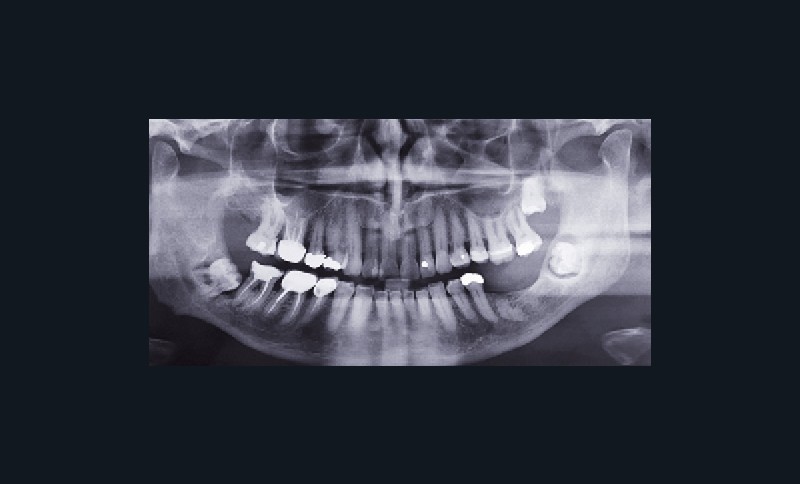

Une dent enclavée (terme utilisé principalement en France) est « une dent dont l’édification radiculaire apicale s’est terminée après que le processus d’éruption…